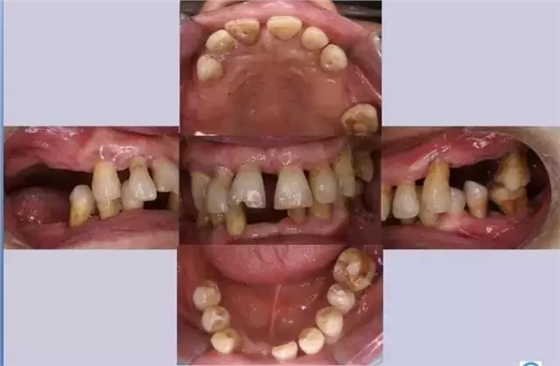

什么是牙周病呢?

牙周病是發(fā)生在牙齒組織周?chē)M織的一種慢性進(jìn)行性疾病。可因牙齦發(fā)生炎癥、水腫、牙周袋形成、牙齒松動(dòng)、咀嚼功能下降所致,最終導(dǎo)致牙齒脫落。臨床晚期時(shí)會(huì)出現(xiàn)牙齦出血、溢膿、牙齒松動(dòng)等癥狀。

640.webp (4).jpg

牙周病的發(fā)病年齡以35歲以后較為多見(jiàn)。如齦炎未能及時(shí)治療,炎癥可由牙齦向深層擴(kuò)散到牙周膜、牙槽骨和牙骨質(zhì)而發(fā)展為牙周病。由于早期多無(wú)明顯自覺(jué)癥狀而易被忽視,待有癥狀時(shí)已較嚴(yán)重,甚至已不能保留牙齒。

640.webp (5).jpg

牙周病癥狀

1牙周袋形成

由于炎癥的擴(kuò)展,牙周膜被破壞,牙槽骨逐漸吸收,牙齦與牙根分離,使齦溝加深而形成牙周袋??捎锰结槣y(cè)牙周袋深度,X線檢查時(shí)可發(fā)現(xiàn)牙槽骨有不同程度的吸收。

2牙周溢膿

牙周袋壁有潰瘍及炎癥性肉芽組織形成,袋內(nèi)有膿性分泌物存留,故輕按牙齦,可見(jiàn)溢膿,并常有口臭。

3牙齒松動(dòng)

由于牙周組織被破壞,特別是牙槽骨吸收加重時(shí),支持牙齒力量不足,出現(xiàn)牙齒松動(dòng)、移位等現(xiàn)象。